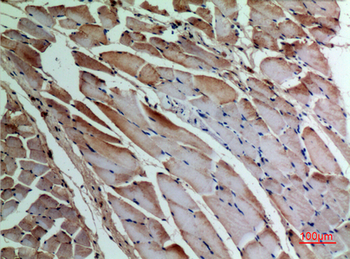

α-SMA Polyclonal Antibody

Catalog Number: orb1411650

| Catalog Number | orb1411650 |

|---|---|

| Category | Antibodies |

| Description | Rabbit polyclonal antibody to α-SMA. |

| Clonality | Polyclonal |

| Species/Host | Rabbit |

| Conjugation | Unconjugated |

| Reactivity | Human, Mouse, Rat |

| UniProt ID | P68133 |

| Tested applications | IHC-P, WB |

| Dilution range | WB: Western Blot: 1/500 - 1/2000. IHC-p: 1:100-300 ELISA: 1/20000. Not yet tested in other applications. |

| Storage | Maintain refrigerated at 2-8°C for up to 2 weeks. For long term storage store at -20°C in small aliquots to prevent freeze-thaw cycles |

| Alternative names | ACTA1; ACTA; Actin, alpha skeletal muscle; Alpha-a Read more... |

| Note | For research use only |